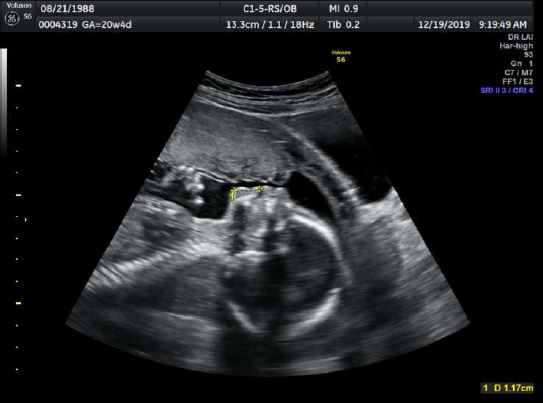

孕期 20w胎兒高層次超音波 胎兒心臟超音波 選擇專業又細心的 孕兒診所 Lu拉拉是對夫妻 痞客邦